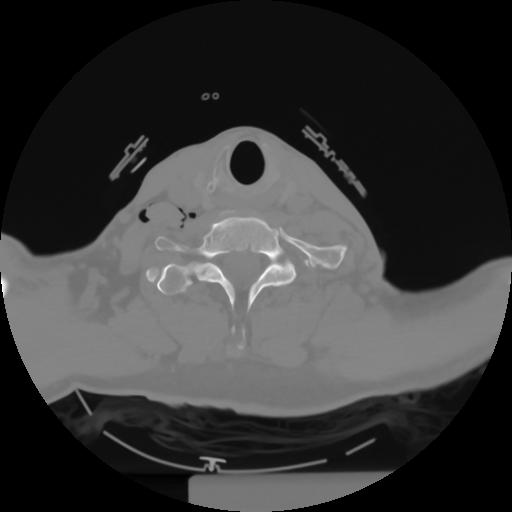

10 P.BLANDAS,,Axial,2.0,P.BLANDAS,,